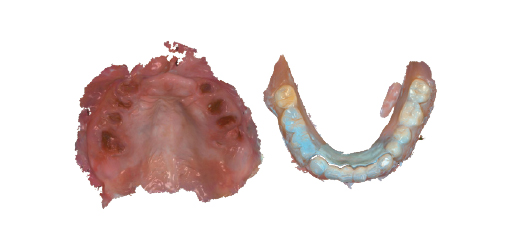

Intraoral scan

If an intraoral scanner is not available, traditional impression taking techniques are adequete

Intraoral scan

If an intraoral scanner is not available, traditional impression taking techniques are adequete

Conventional Workflow

Apply JB Fork to upper and lower jaws

Apply JB Fork to upper and lower jaws